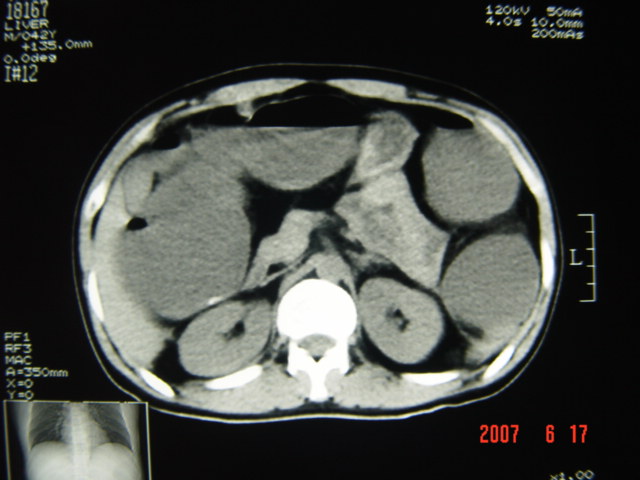

[br][br]以下是引用lkc8963在2007-6-17 13:32:00的发言:[br]完全支持邓主任意见:降/乙交界部占位性病变伴不全梗阻.做个增强或者be可能更好.